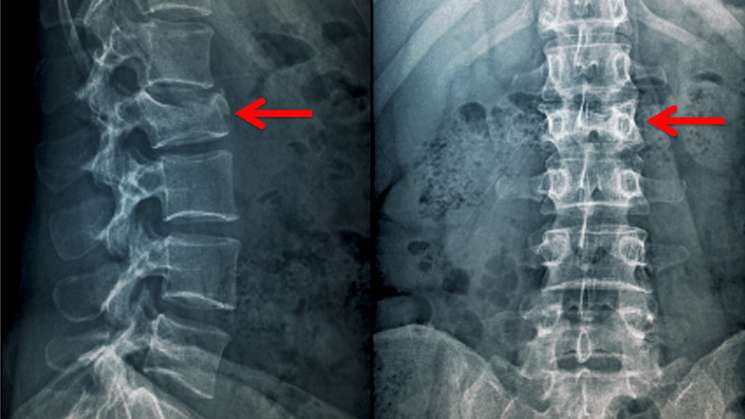

Las fracturas vertebrales ocurren cuando el bloque óseo o el cuerpo vertebral de la columna colapsa, lo que provoca dolor intenso, deformidad y pérdida de altura, las cuales suelen ser causadas por osteoporosis debido a huesos débiles y quebradizos, explica la especialista.

Giustina explicó que una radiografía de tórax simple puede detectar esas fracturas y se debe realizar una evaluación morfométrica en los pacientes con la Covid-19 al momento del ingreso hospitalario.

La investigación se basa en radiografías de 114 pacientes con Covid-19 y detectó fracturas vertebrales torácicas en un 35 por ciento, al tiempo que dichas personas afectadas también por hipertensión arterial y enfermedades cardíacas tenían más probabilidades de necesitar ventiladores.